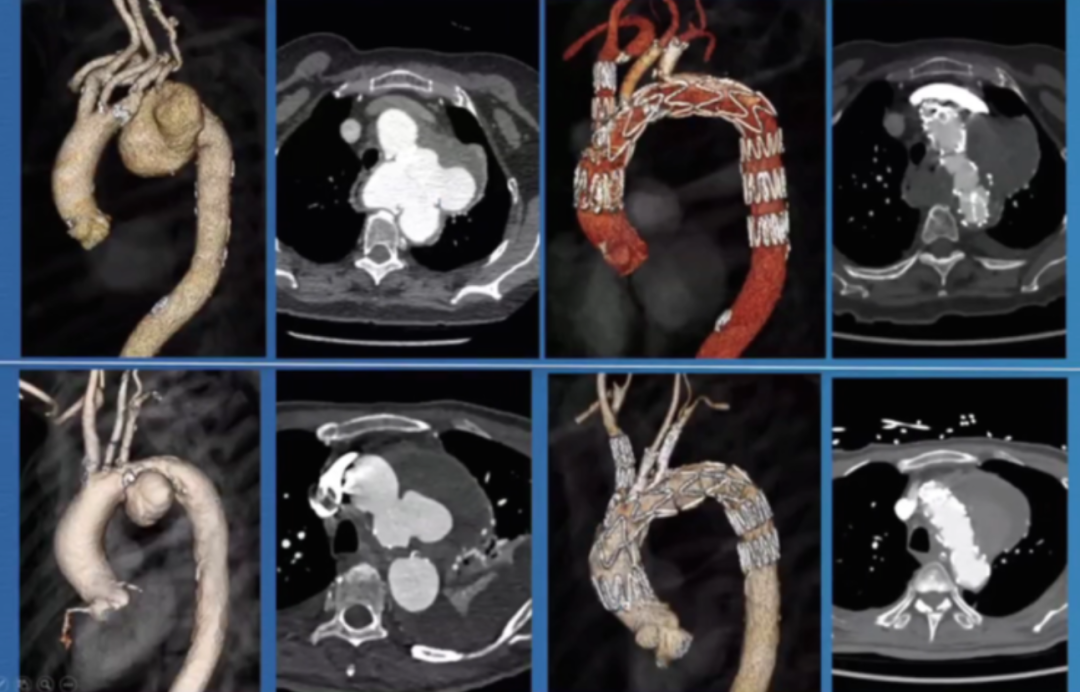

单中心中期结果(Cookvs Terumo)

针对“内部分支型主动脉弓支架(Inner Branched Arch Endo graft)”,中国的一家中心对比了Cook A Branch与Terumo Double Branch两种支架的临床表现,共纳入97例患者(Cook10例,Terumo87例,含11例急诊),中期随访结果如下:Cook 组纳入 54 例(11 例为急诊病例),技术成功率未明确,严重中风发生率 5.9%,短暂性中风发生率 7.8%;Terumo 组纳入 43 例(10 例为急诊病例)。同时在高死亡率、再干预等指标上也存在不同数据表现,可用于分析两种治疗手段在疗效等方面的差异。

研究表明逆⾏A型夹层的发生率较高,除了其近端锚定区选择不当会增加⻛险外,对于亚洲患者解剖特点也会有一定的风险,入⼸部直径超过40mm时,伴有⾎栓时⼿术难度增加;中国患者更年轻,夹层常延伸⾄左颈总动脉起始部。现有器械在亚洲患者中常⾯临锚定区不⾜的问题。

香港玛丽医院分享了38例主动脉弓分支支架植入病例的经验,其中28例为A/Br型,8例为B/Br型,1例为L型,患者平均年龄75.5岁,男性34例。30天死亡率为7.8%,手术中风率10.5%(2例严重+2例轻微),再干预率21%,逆行夹层3例,动脉瘤相关死亡2例。

此外,报告强调了健康主动脉的重要性,升主动脉直径<38mm是关键标准。曾有案例显示,在40mm主动脉植入支架后发生灾难性逆行A型夹层,这警示临床医生必须在健康主动脉段锚定,避免在夹层病理区域进行操作。